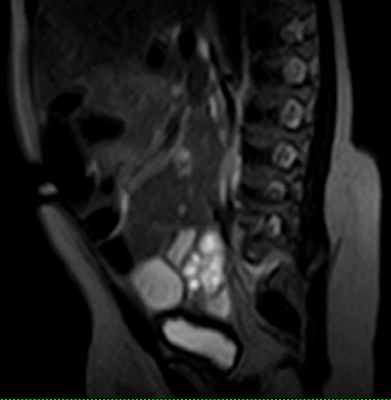

Липомиеломенингоцеле.

Покрытые кожей глубоко залегающие липоматозные массы.

(слева) МРТ: внутримозговые массы, связанные с подкожной липомой.

Обратите внимание на низкое завершение спинного мозга на верхнем полюсе липомы.

24.07.2012 г. МРТ пояснично-крестцового отдела позвоночника девочка 2 мес Липомиеломенингоцеле. КОНКУРС.

На МРТ пояснично-крестцового отдела определяяетмя подкожная липома , к оторая через дефект (ращепление) дужек сакральных позвонков распространяетя в позвоночный канал, соединяеясь на этом уровне с аномально низко расположеным спинном мозгм (Tethered spinal cord syndrome). Также мы видим выхождение спинного мозга и оболочек через дефект дужек сакральных позввонков. Такая врожденная аномалия развития позвоночника и спинного мозга называется - ЛИПОМИЕЛОМЕНИНГОЦЕЛЕ.(вариант спинального дизарфизма).